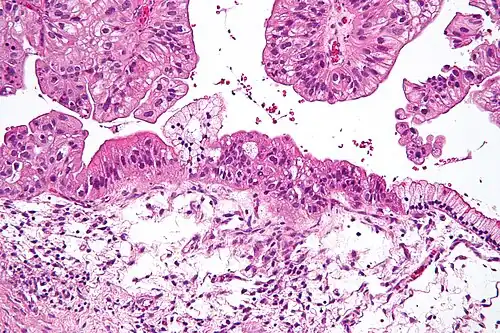

| Micrograph of a mucinous ovarian carcinoma stained by H&E | |

Ovarian cancer is a cancerous tumor of an ovary.[10] It may originate from the ovary itself or more commonly from communicating nearby structures such as fallopian tubes or the inner lining of the abdomen.[3][11] The ovary is made up of three different cell types including epithelial cells, germ cells, and stromal cells.[12] When these cells become abnormal, they have the ability to divide and form tumors. These cells can also invade or spread to other parts of the body.[13] When this process begins, there may be no or only vague symptoms.[1] Symptoms become more noticeable as the cancer progresses.[1][14] These symptoms may include bloating, vaginal bleeding, pelvic pain, abdominal swelling, constipation, and loss of appetite, among others.[1] Common areas to which the cancer may spread include the lining of the abdomen, lymph nodes, lungs, and liver.[15]

Pathology

Ovarian cancers are classified according to the microscopic appearance of their structures (histology or histopathology). Histology dictates many aspects of clinical treatment, management, and prognosis. The gross pathology of ovarian cancers is very similar regardless of histologic type: ovarian tumors have solid and cystic masses.[29] According to SEER, the types of ovarian cancers in women age 20 and over are:[66]

Ovarian cancers are histologically and genetically divided into type I or type II. Type I cancers are of low histological grade and include endometrioid, mucinous, and clear-cell carcinomas. Type II cancers are of higher histological grade and include serous carcinoma and carcinosarcoma.[28]

Mucinous

Mucinous tumors include mucinous adenocarcinoma and mucinous cystadenocarcinoma.[29]

Mucinous adenocarcinoma

Mucinous adenocarcinomas make up 5–10% of epithelial ovarian cancers. Histologically, they are similar to intestinal or cervical adenocarcinomas and are often actually metastases of appendiceal or colon cancers. Advanced mucinous adenocarcinomas have a poor prognosis, generally worse than serous tumors, and are often resistant to platinum chemotherapy, though they are rare.[29]